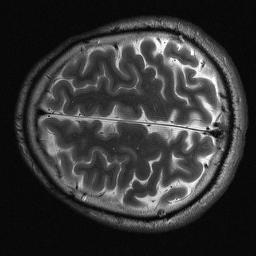

Magnetic resonance imaging serves as an essential tool for clinical diagnosis. However, it suffers from a long acquisition time. The utilization of deep learning, especially the deep generative models, offers aggressive acceleration and better reconstruction in magnetic resonance imaging. Nevertheless, learning the data distribution as prior knowledge and reconstructing the image from limited data remains challenging. In this work, we propose a novel Hankel-k-space generative model (HKGM), which can generate samples from a training set of as little as one k-space data. At the prior learning stage, we first construct a large Hankel matrix from k-space data, then extract multiple structured k-space patches from the large Hankel matrix to capture the internal distribution among different patches. Extracting patches from a Hankel matrix enables the generative model to be learned from redundant and low-rank data space. At the iterative reconstruction stage, it is observed that the desired solution obeys the learned prior knowledge. The intermediate reconstruction solution is updated by taking it as the input of the generative model. The updated result is then alternatively operated by imposing low-rank penalty on its Hankel matrix and data consistency con-strain on the measurement data. Experimental results confirmed that the internal statistics of patches within a single k-space data carry enough information for learning a powerful generative model and provide state-of-the-art reconstruction.